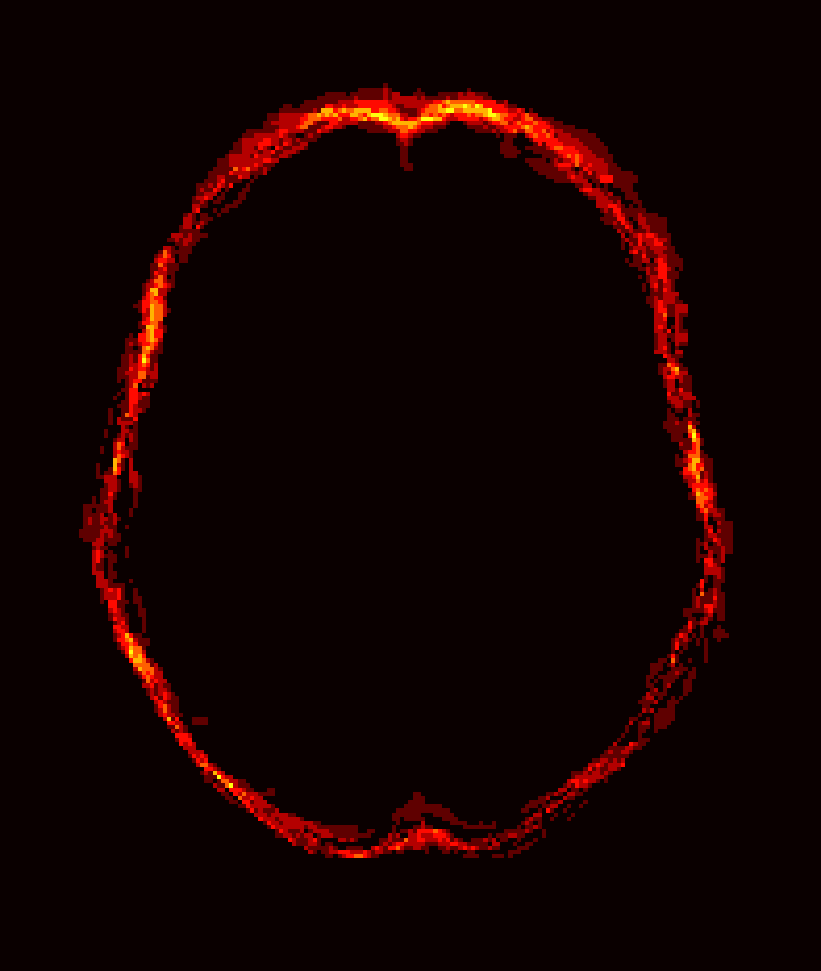

Fig. 1 shows example images from each dataset to illustrate image variability. IBSR and LPBA40 contain images from normal subjects and include large portions of the neck; BRATS has very low out-of-plane resolution; and the TBI dataset contains large pathologies and abnormal skulls.

Refer to caption

Figure 1: Illustration of image appearance variability on a selection of images from each (evaluation) database. From top to bottom: IBSR, LPBA40, BRATS and TBI.